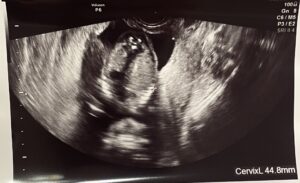

ちなみにこちらは普通のエコー写真です。頭が右側で体が左側の横向きで、お顔は上を向いています。

目は穴になってうつってしまうけどちゃんとあるよ、と前にお医者さんが言っていました。